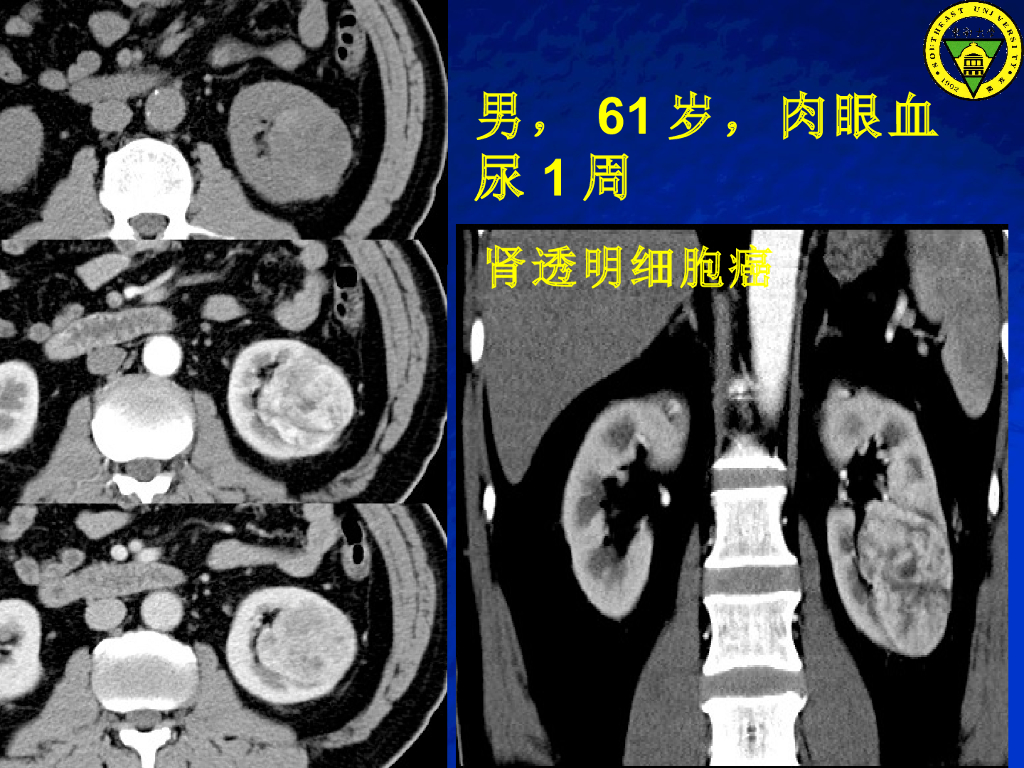

《放射诊断学》演示文稿-泌尿系肿瘤实习课.pdf